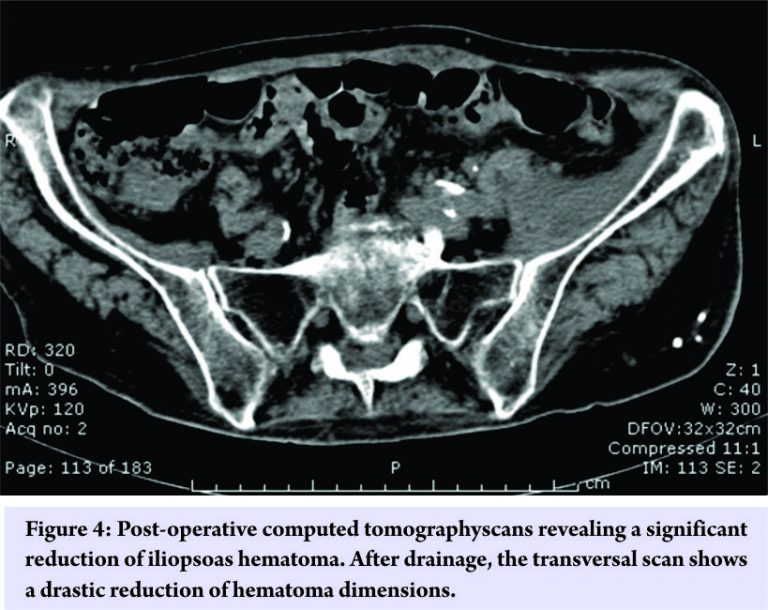

Electromyography (EMG) and nerve conduction study were performed, and they evidenced a compression of the left femoral nerve with the weakness of left vastus medialis, vastus lateralis, and iliopsoas muscles. Blood tests only revealed a mild anemia (hemoglobin was 9,7 g/dL), and no alterations of coagulation, renal function, and liver function were found. Given the severe pain and functional disability, we decided to perform surgery to drain the hematomas. We decided to use the first window of the ilioinguinal approach to reach the greatest one, and in our opinion, the most compressive one on the neurovascular bundle. The biggest hematoma was found between iliac muscle and iliac fossa and was drained, extracting about 280 cc of blood partly clotted. Post-operative CT scan of the abdomen and pelvis evidenced a drastic size reduction of the hematomas (Fig. 4). Even if neurological deficits remained, inguinal pain disappeared immediately after surgery, and 4 weeks after surgery, the patient was able to stand up and to walk using a walker for small distances. The patient underwent a protocol of physical rehabilitation, and after 6 months, she was able to walk with crutches, and a new EMG documented a partial recovery of left femoral nerve lesion.